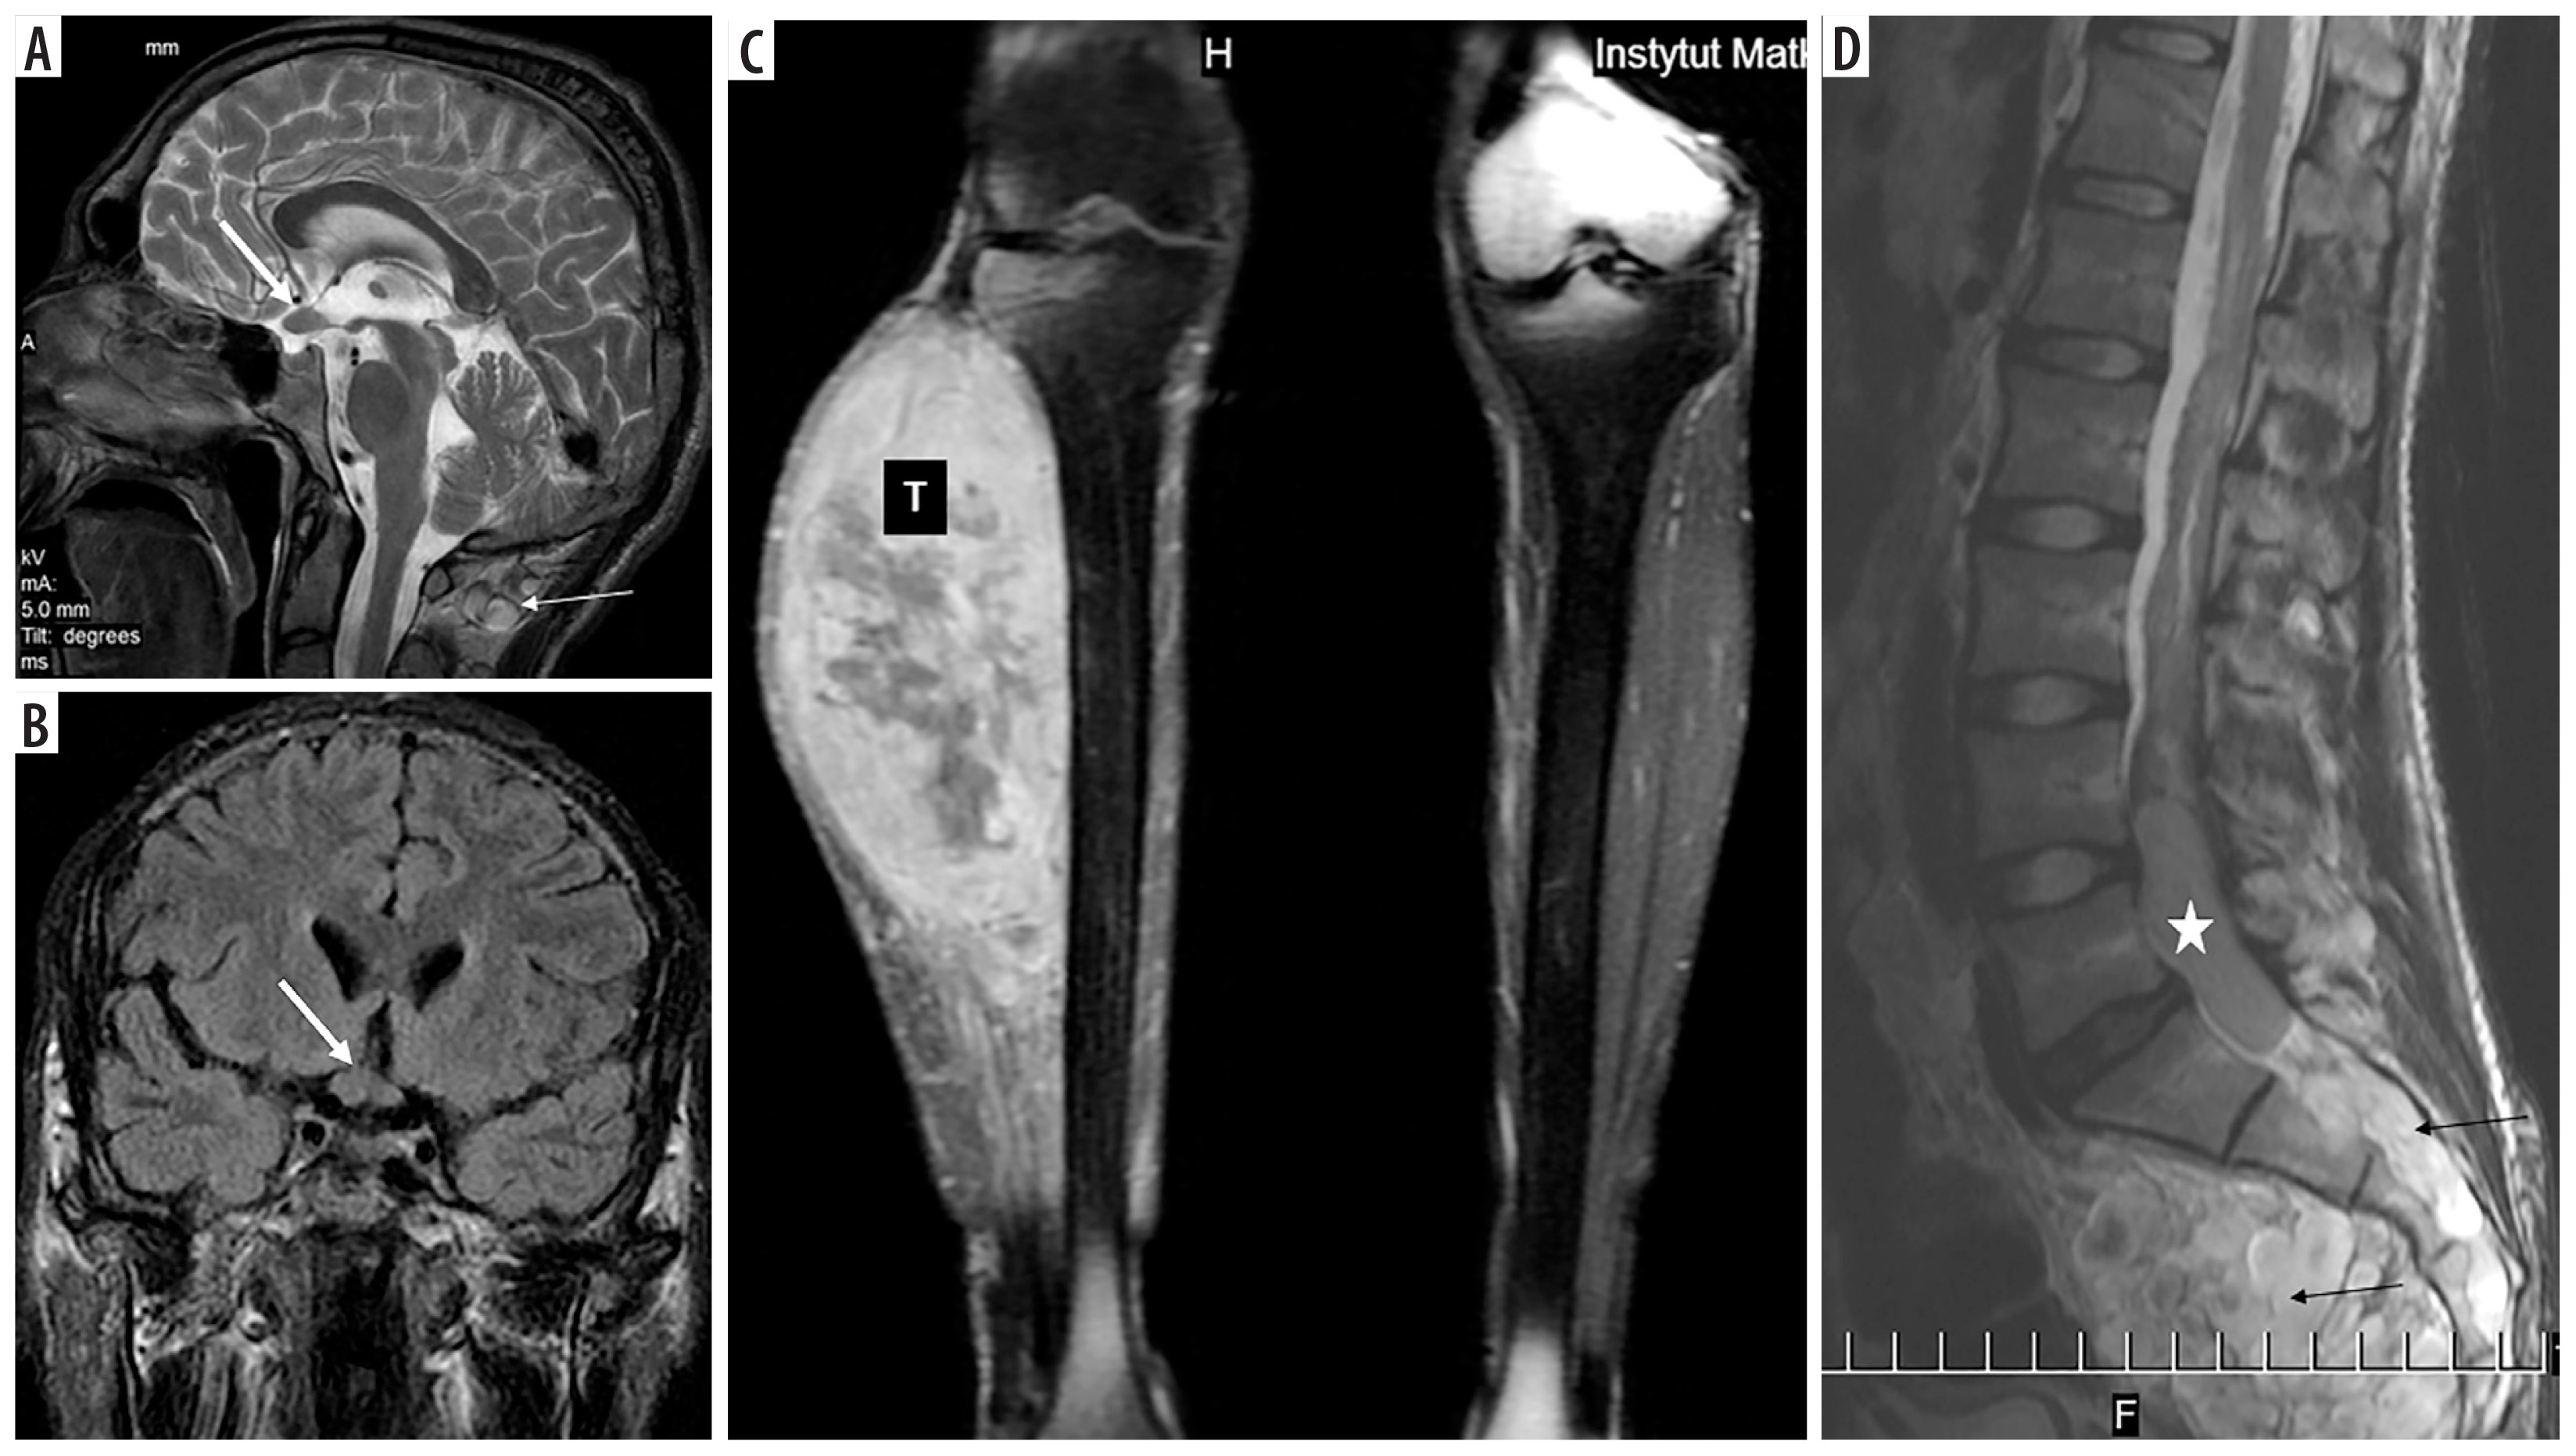

Figure 5

NF1 patient (No. 55). Optic chiasm glioma (thick arrows) known since the age of at least 14 years (first available brain MRI): A) T2-weighted sagittal image, B) coronal FLAIR section. MPNST (marked with “T”) of the right calf at the age of 20: C) coronal T1-weighted image with fat saturation and contrast enhancement. Ependymoma (asterisk) of the spinal canal at the age of 22: D) sagittal T2-weighted image. Thin arrows indicate multiple neurofibromas

NF1 also belongs to CPS and is characterized by RAS signaling pathway dysfunction. In a Swiss paper, NF1 (and 2) constituted the largest group of CPS identified in 8074 childhood cancer patients [6]. NF1 is an interesting disease in that the spontaneous regression of tumors can occur in its course. In our material of NF1 there are 2 cases of spontaneous regression of hypothalamic tumors, most likely gliomas [17]. In our 4 patients with NF1 who were included in this study, the IT was an optic-pathway glioma, which is a WHO grade 1 pilocytic astrocytoma. One patient (No. 59) had another, hemispheric pilocytic astrocytoma, WHO 1. Two of them had 2 subsequent malignancies each; in 1 out of these 2 (No. 53), the third tumor (MPNST) was most likely secondary to the second one (RMS), in the field of irradiation. In the second one (No. 55), ependymoma in the lumbar-sacral part of the spinal canal was diagnosed. Ependymomas are associated with neurofibromatosis type 2, but in the literature case reports of ependymoma in NF1 – although very rarely – can also be found [18]. In the peripheral nervous system there is a risk of MPNST that arise in pre-existing plexiform neurofibromas, typical of this disease. RMS is the most common soft tissue sarcoma in children, and its prevalence in NF1 is about 20 times higher than that in the general population [19].